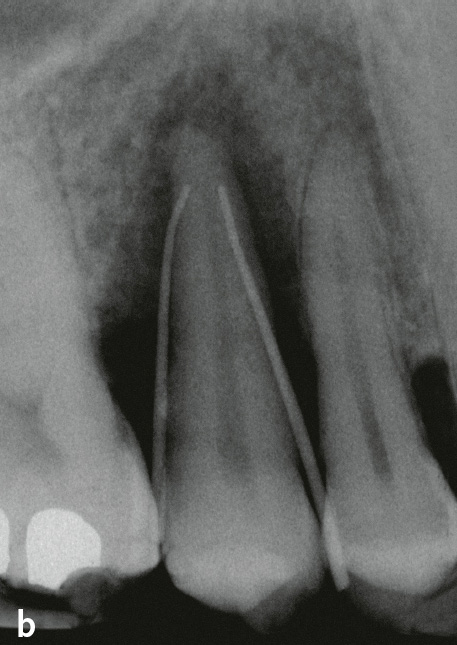

Abb. 9 Palatinaler Knochendefekt primär parodontalen Ursprungs, dessen apikale Ausdehnung sich als periapikale hypodense (radiotransluzente) Zone auf das Röntgenbild projiziert: a) schematisch (nach10); b) Röntgenbild von Zahn 15 mit Guttaperchaspitzen in den parodontalen Taschen (Sondierungstiefen [ST] an allen 3 palatinalen Stellen 11 mm, Mobilität Grad III)11; c) Röntgenbild 7 Monate nach Schienung mit Komposit in Säure-Ätz-Technik und subgingivaler Instrumentierung mit systemischer Antibiotikagabe: knöcherne Auffüllung, ST maximal 5 mm11.

Auch die Geschwindigkeit, mit der eine Läsion voranschreitet, kann Hinweise auf die Genese geben: Parodontitis ist eine chronische Erkrankung mit zumeist langwierigem Verlauf. Entsteht isoliert an einer Stelle innerhalb von nur 2 Jahren ein Knocheneinbruch, der bis ins apikale Wurzeldrittel reicht, sind eine primär endodontale Genese oder eine vertikale Wurzelfraktur sehr wahrscheinlich (Tab. 2). Ein weiteres Unterscheidungskriterium kann die Form der knöchernen Läsionen sein: Nach koronal weite und sich nach apikal v-förmig verengende Defekte weisen auf Läsionen primär parodontalen Ursprungs hin, während runde und halbrunde Querschnitte, bei denen sich der Knochen nach koronal wieder verengt, eher auf primär endodontale Läsionen hinweisen (Tab. 2, Abb. 10). Die knöcherne Läsion hat dort ihren größten Durchmesser, wo sie ihren Ausgang nahm.

Abb. 10 Der endodontal verursachte Entzündungsprozess zerstört die Verbindung zwischen den im Knochen und im Wurzelzement verankerten Desmodontalfasern. Der proximale Anteil dieser Fasern bleibt aber anscheinend zumindest anfangs intakt (Abb. 5), sodass sich nach Eliminierung der endodontalen Entzündungsursache durch Wurzelkanalbehandlung die Kontinuität der Desmodontalfasern wiederherstellen kann. Röntgenaufnahmen von Zahn 22, der bei Erstbefundung asensibel auf Kältetest reagierte: August 1997: Masterpoint-Röntgenaufnahme: Distal erstreckt sich eine knöcherne Läsion vom Limbus alveolaris bis zum Apex. Die knöcherne Läsion hat ihre größte Ausdehnung im apikalen Wurzeldrittel; September 2000: nahezu vollständige Auffüllung des Knochendefekts nach Desinfektion und Füllung des Wurzelkanals.